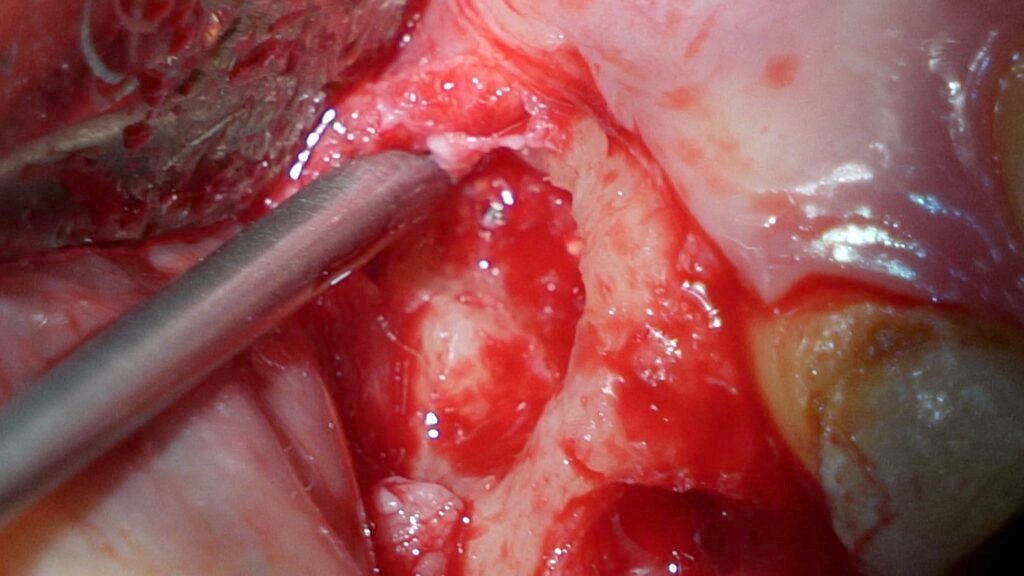

I then extracted the tooth, which showed overfilled canals, but unfortunately, the broken file did not come out with the tooth. A follow-up X-ray confirmed the file remained in the bone. Using a high-magnification microscope and special illumination, I performed a surgical procedure to carefully remove the broken file from the bone. The patient’s discomfort was resolved after a few days, and she recovered well.